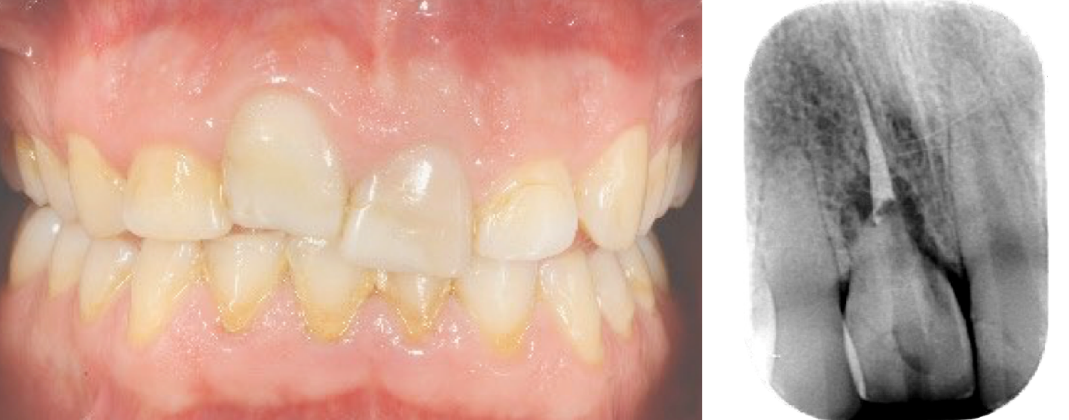

Il caso clinico del Professor Soardi illustra chiaramente i risultati estremamente interessanti che si riescono ad ottenere attraverso il protocollo Open Barrier Tecnique, attraverso un approccio minimamente invasivo ed utilizzando materiali e metodi testati. Come potrete vedere dal risultato finale anche una situazione così difficilmente recuperabile, in altissima zona estetica, può essere gestita e risolta ottimamente.

Immagine clinica iniziale ed evidenza radiografica del riassorbimento radicolare